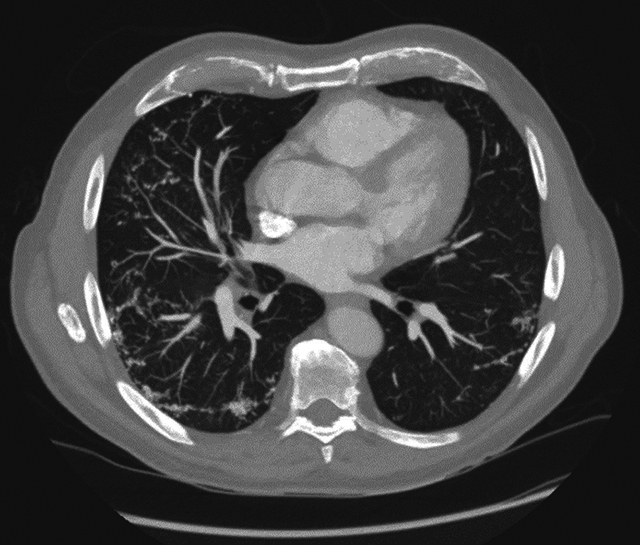

Teaching point: Dendriform pulmonary ossifications (DPO) are a rare form of diffuse pulmonary ossifications, in which these ossifications are organised in dendrite-like lines in the periphery of the bases of the lung, most commonly attributed to underlying interstitial lung disease (ILD), but can also be found in patients with chronic aspiration if no other CT findings of ILD are present.

教学要点树枝状肺骨化(DPO)是一种罕见的弥漫性肺骨化,这些骨化呈树枝状排列在肺底部外围,最常见的原因是潜在的间质性肺病(ILD),但如果 CT 没有发现其他 ILD 病变,也可在慢性吸入性肺病患者中发现。